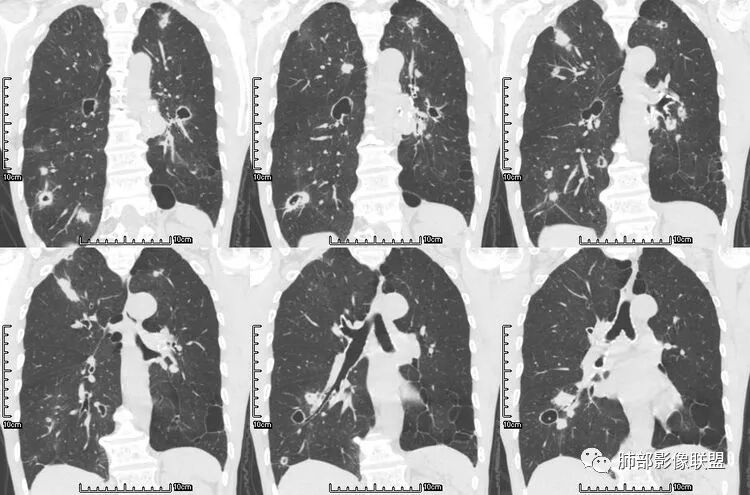

病史为结肠腺癌;双肺多发薄壁囊腔转移瘤

来源于杨凌婧.囊性空洞型肺转移瘤1例报告[J].实用医院临床杂志,2016,13(01):157-158.